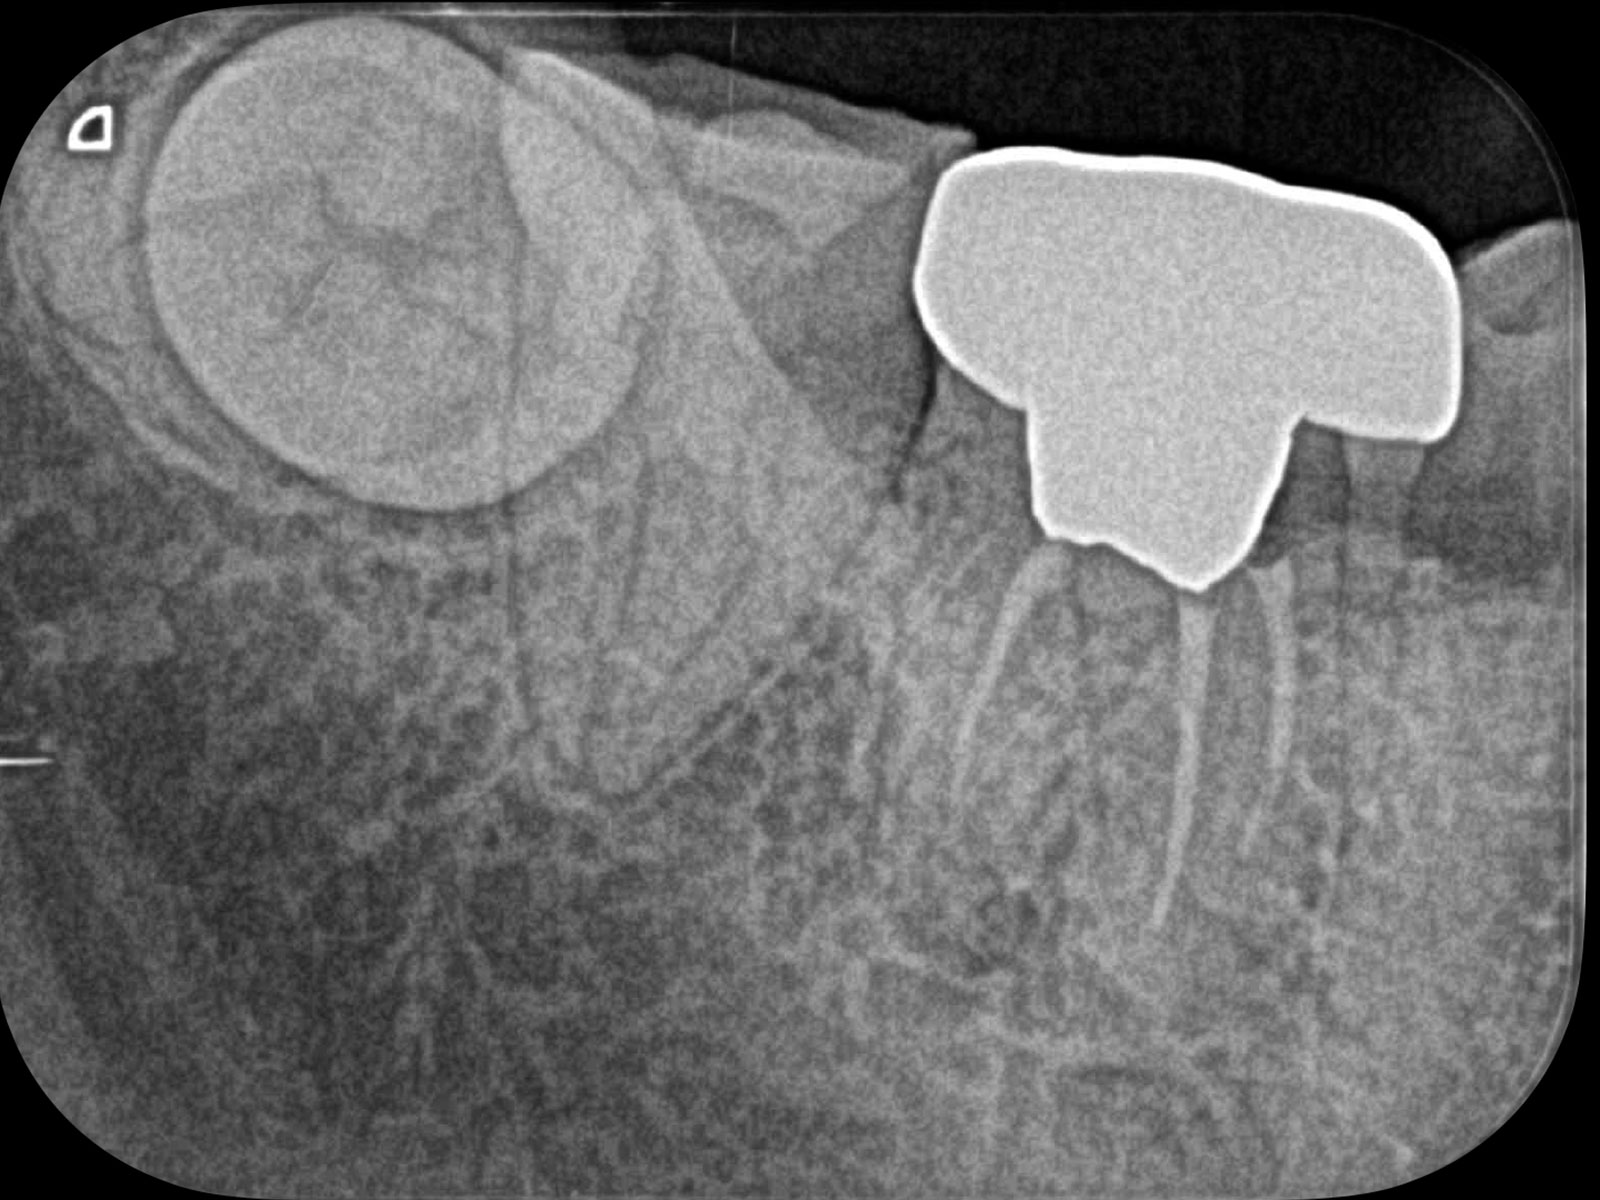

主訴: 右下がしみて痛い。

右下7根の根幹治療と親知らずの抜歯